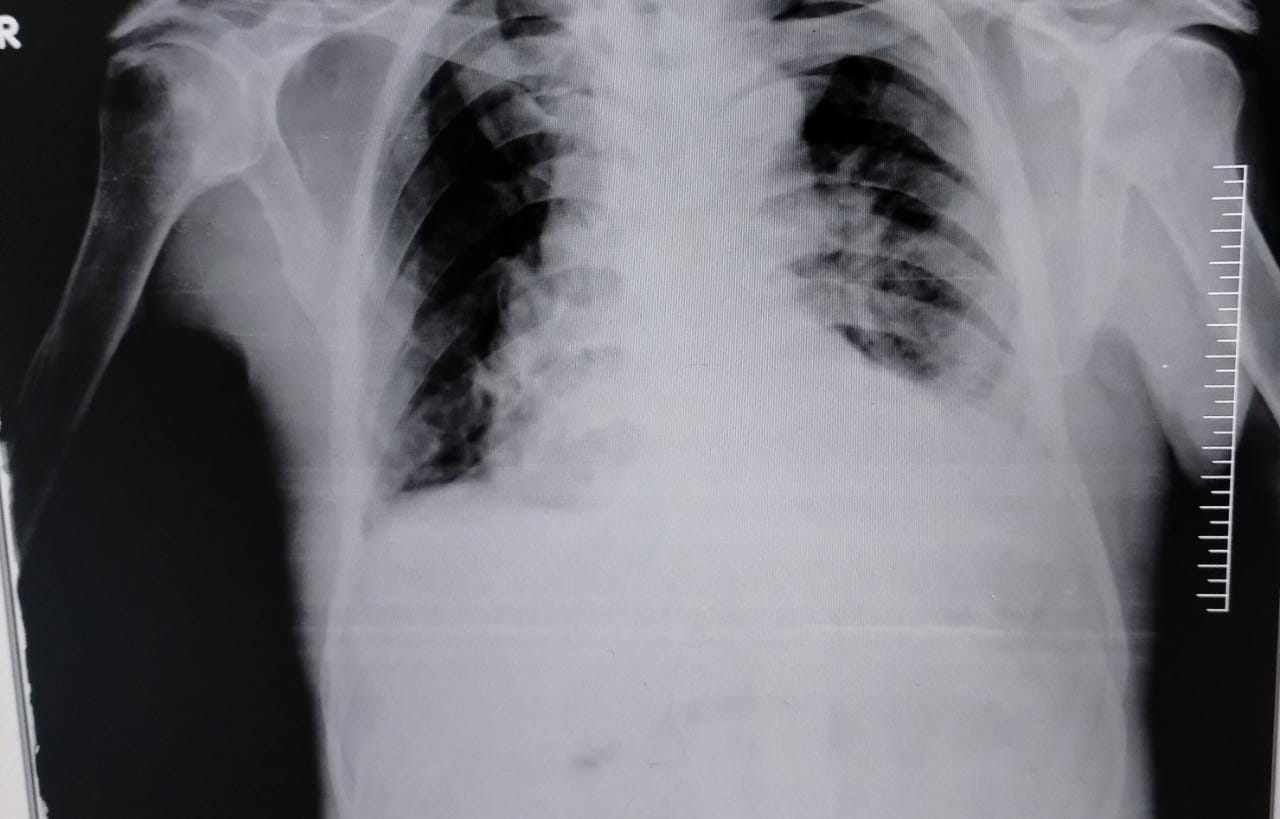

Chest X Ray

BILATERAL PLEURAL EFFUSION (RIGHT MORE THAN LEFT) WITH UNDERLYING COLLAPSE.